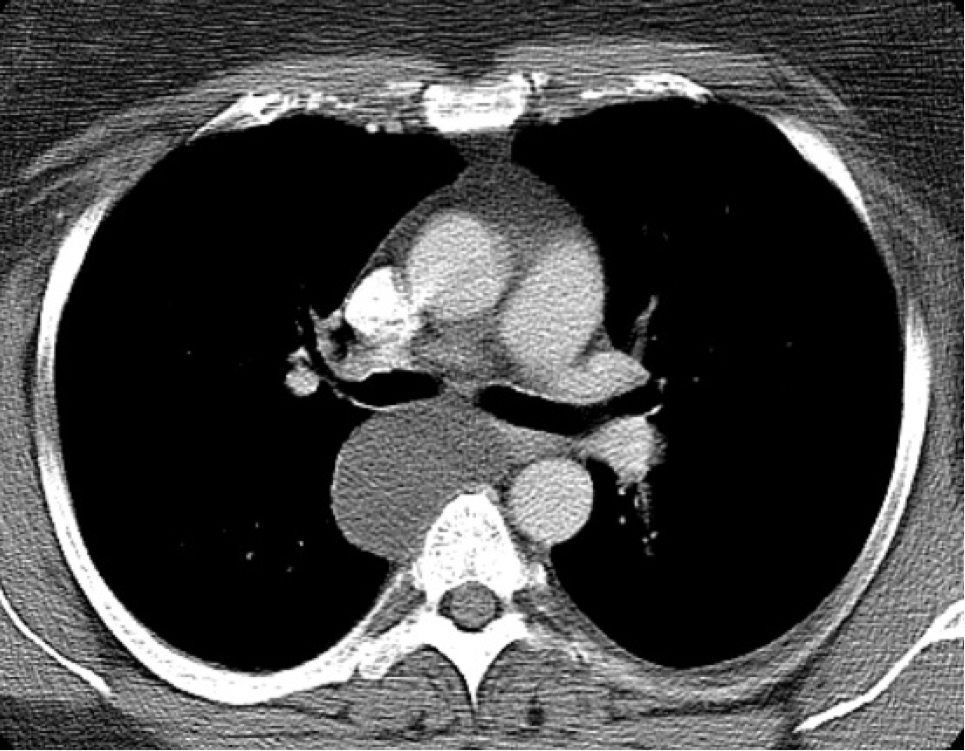

Q

What is this?

A

bronchopulmonary sequestration (arrow points to it’s separate blood supply from aorta)